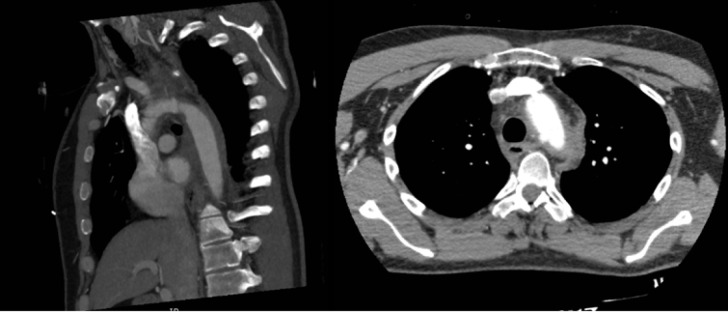

Case presentation: A 36-year-old male was transferred following a fire suppressant explosion at a copper smelter. He presented with central chest pain and stable hemodynamics, with no signs of external chest trauma. Computed tomography (CT) imaging revealed a localized dissection of the ascending aorta and a partial rupture of the aortic arch, in addition to fractures in the hand and foot caused by suppressant debris. The patient subsequently became hemodynamically unstable and required urgent surgical intervention. He underwent ascending aortic and aortic arch repairs. Postoperatively, his course was complicated by a pulmonary embolism, which was managed medically. He was eventually discharged after recovering from his injuries.